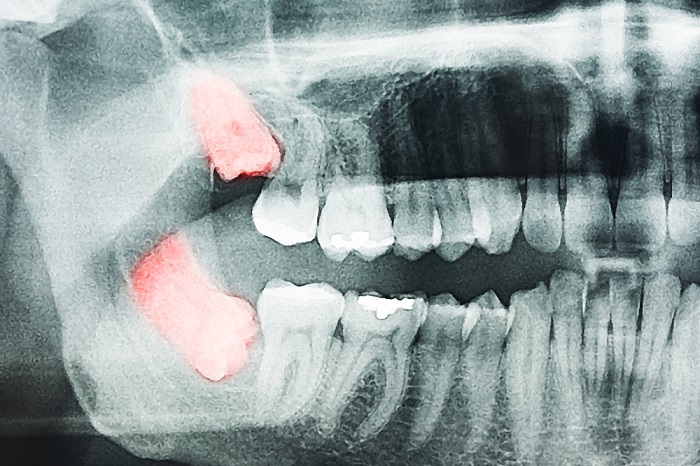

La erupción de las muelas del juicio puede causar molestias:, mover los dientes, causar dolores y provocar más visitas al dentista entre otras ‘lindeces’. Pese a las múltiples hipótesis sobre su origen, este seguía siendo un tema que generaba controversia entre los expertos, hasta que Alistair Evans, de la Universidad de Monash (Australia), a partir de un modelo teórico del desarrollo de la dentición en los mamíferos, decidió investigar si ese modelo se aplica en los homínidos. Esta teoría se basa en que un diente cuando se desarrolla emite señales al resto de dientes y la proporción entre estas señales es la que determina el tamaño de los dientes vecinos.

La investigación revela que el modelo puede explicar la degeneración del tercer molar hasta convertirse en la conocida muela del juicio ya que, con la aparición de nuestro género (Homo), la disminución de las dimensiones de la dentadura conllevó a su vez una reducción del tercer molar.

La erupción de las muelas del juicio puede verse acompañada de una infección en la encía (pericoronaritis) y a la vez puede provocar la aparición de caries, por lo que cabe extremar la higiene bucal durante ese periodo. Un correcto cepillado con una pasta dentífrica acorde a tus necesidades bucodentales y el uso imprescindible de la seda dental y el colutorio son la mejor manera de prevenir complicaciones.